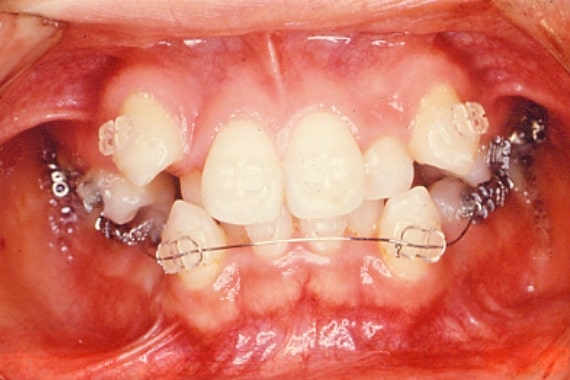

イメージ

矯正装置を歯に装着し、歯の移動を開始します。

矯正装置は、金属ブラケットの他に、目立ちにくい白色の装置や、歯の裏側につける舌側矯正装置もあります。

通院は通常3~4週間に1回程度で、1回の治療時間は口腔ケアに重点を置きますので約60分です。

治療期間は約2~3年程度が目安となります。